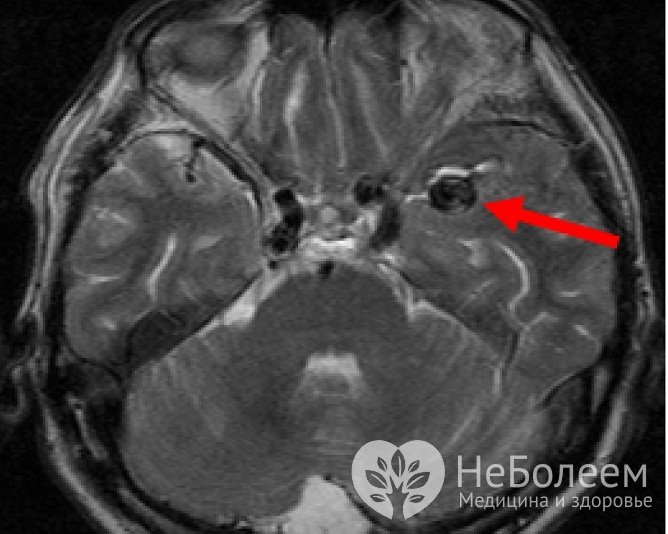

При бессимптомном течении аневризмы сосудов головного мозга обычно становятся случайными диагностическими находками, обнаруживаемыми при обследовании пациента по иному поводу. При появлении клинической симптоматики церебральная аневризма диагностируется на основании имеющейся неврологической симптоматики, а также данных инструментальных исследований, к которым относятся:

Аневризма сосудов головного мозга на МРТОбнаружение крови в цереброспинальной жидкости, полученной в ходе люмбальной пункции, – подтверждение разрыва аневризмы сосудов головного мозга.

Опухолеподобные формы церебральной аневризмы требуют дифференциальной диагностики с объемными процессами головного мозга (абсцессом, кистой, опухолью). При апоплексической форме заболевания проводится дифференциальная диагностика с менингитом, ишемическим инсультом, преходящими нарушениями мозгового кровообращения, приступом эпилепсии.